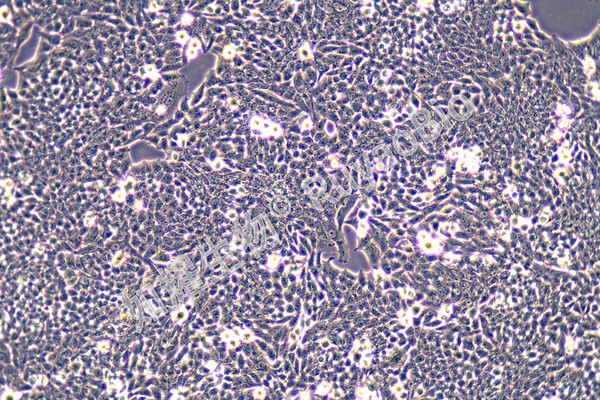

RY-H0181-3.jpg

人肝癌阿奇霉素耐药株